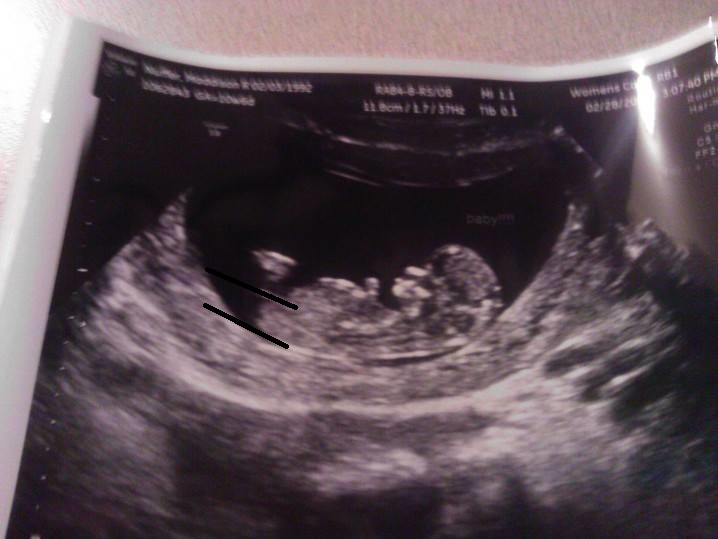

Hi this is my first post here! I just had my first scan yesterday and the tech said she thinks it looks like a girl! We spent 10 minutes getting good shots of the nub! Anyways it seems kinda long and big? And im having some doubts =/ Attachment 17261Attachment 17262

In the second pic it looks like a split in the end of the nub..... Oh and 11 weeks 6 days!

is it normal for a girl nub to be so thick and long?

Boy I think. The nub looks stacked and it was before 12 weeks so plenty of time to rise xx

It also ends at the bum whereas many girl nubs extend past it xx

I would guess boy, the nub looks stacked and on the rise for so early. Fingers crossed for pink :)